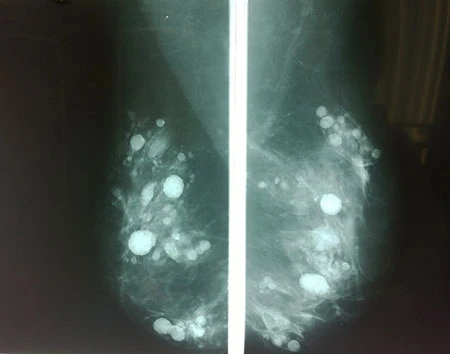

Trước đó bệnh nhân đã đi khám nhiều nơi, sau đó đến khám tại khoa Ung bướu, BV quận Thủ Đức vì cảm giác đau và lợn cợn tại vú kéo dài và lo sợ vì nghĩ mình bị khối u sẽ gây ung thư. Kết quả chẩn đoán hình ảnh cho thấy tuyến vú của bệnh nhân có rất nhiều nốt, dầy đặc trong mô vú, không thể phân biệt với khối u nên không thể lấy từng cục silicon được. Sau khi được tư vấn, bệnh nhân đã chấp nhận cắt hết toàn bộ mô vú để giải phóng khỏi các khối silicon.

Theo BS Vũ, silicon lỏng rất phổ biến trong lĩnh vực thẩm mỹ cách nay khoảng 20 năm, dựa trên đặc tính trơ, ít gây dị ứng và làm đầy nên rất nhiều bác sĩ cũng như dân nghiệp dư sử dụng nhằm nâng ngực, nâng mũi, xóa nếp nhăn …Tuy nhiên sau thời gian sử dụng người ta nhận thấy silicon lỏng có rất nhiều tác dụng phụ như gây loét kéo dài, đau, co rút biến dạng, tạo cục hoặc di chuyển vô phổi, thận… Đặc biệt khi tiêm vào vú, sau thời gian silicon kết thành khối gây nhiều nốt trong vú, rất khó phân biệt với khối u, do đó nếu bệnh nhân chẳng may bi ung thư sẽ khó phát hiện sớm. Do đó, năm 1991 Cơ quan quản lý thực phẩm và dược phẩm Mỹ (FDA) đã ban hành lệnh cấm sử dụng silicon lỏng nhằm mục đích thẩm mỹ, trừ một số ít chỉ định đặc biệt.